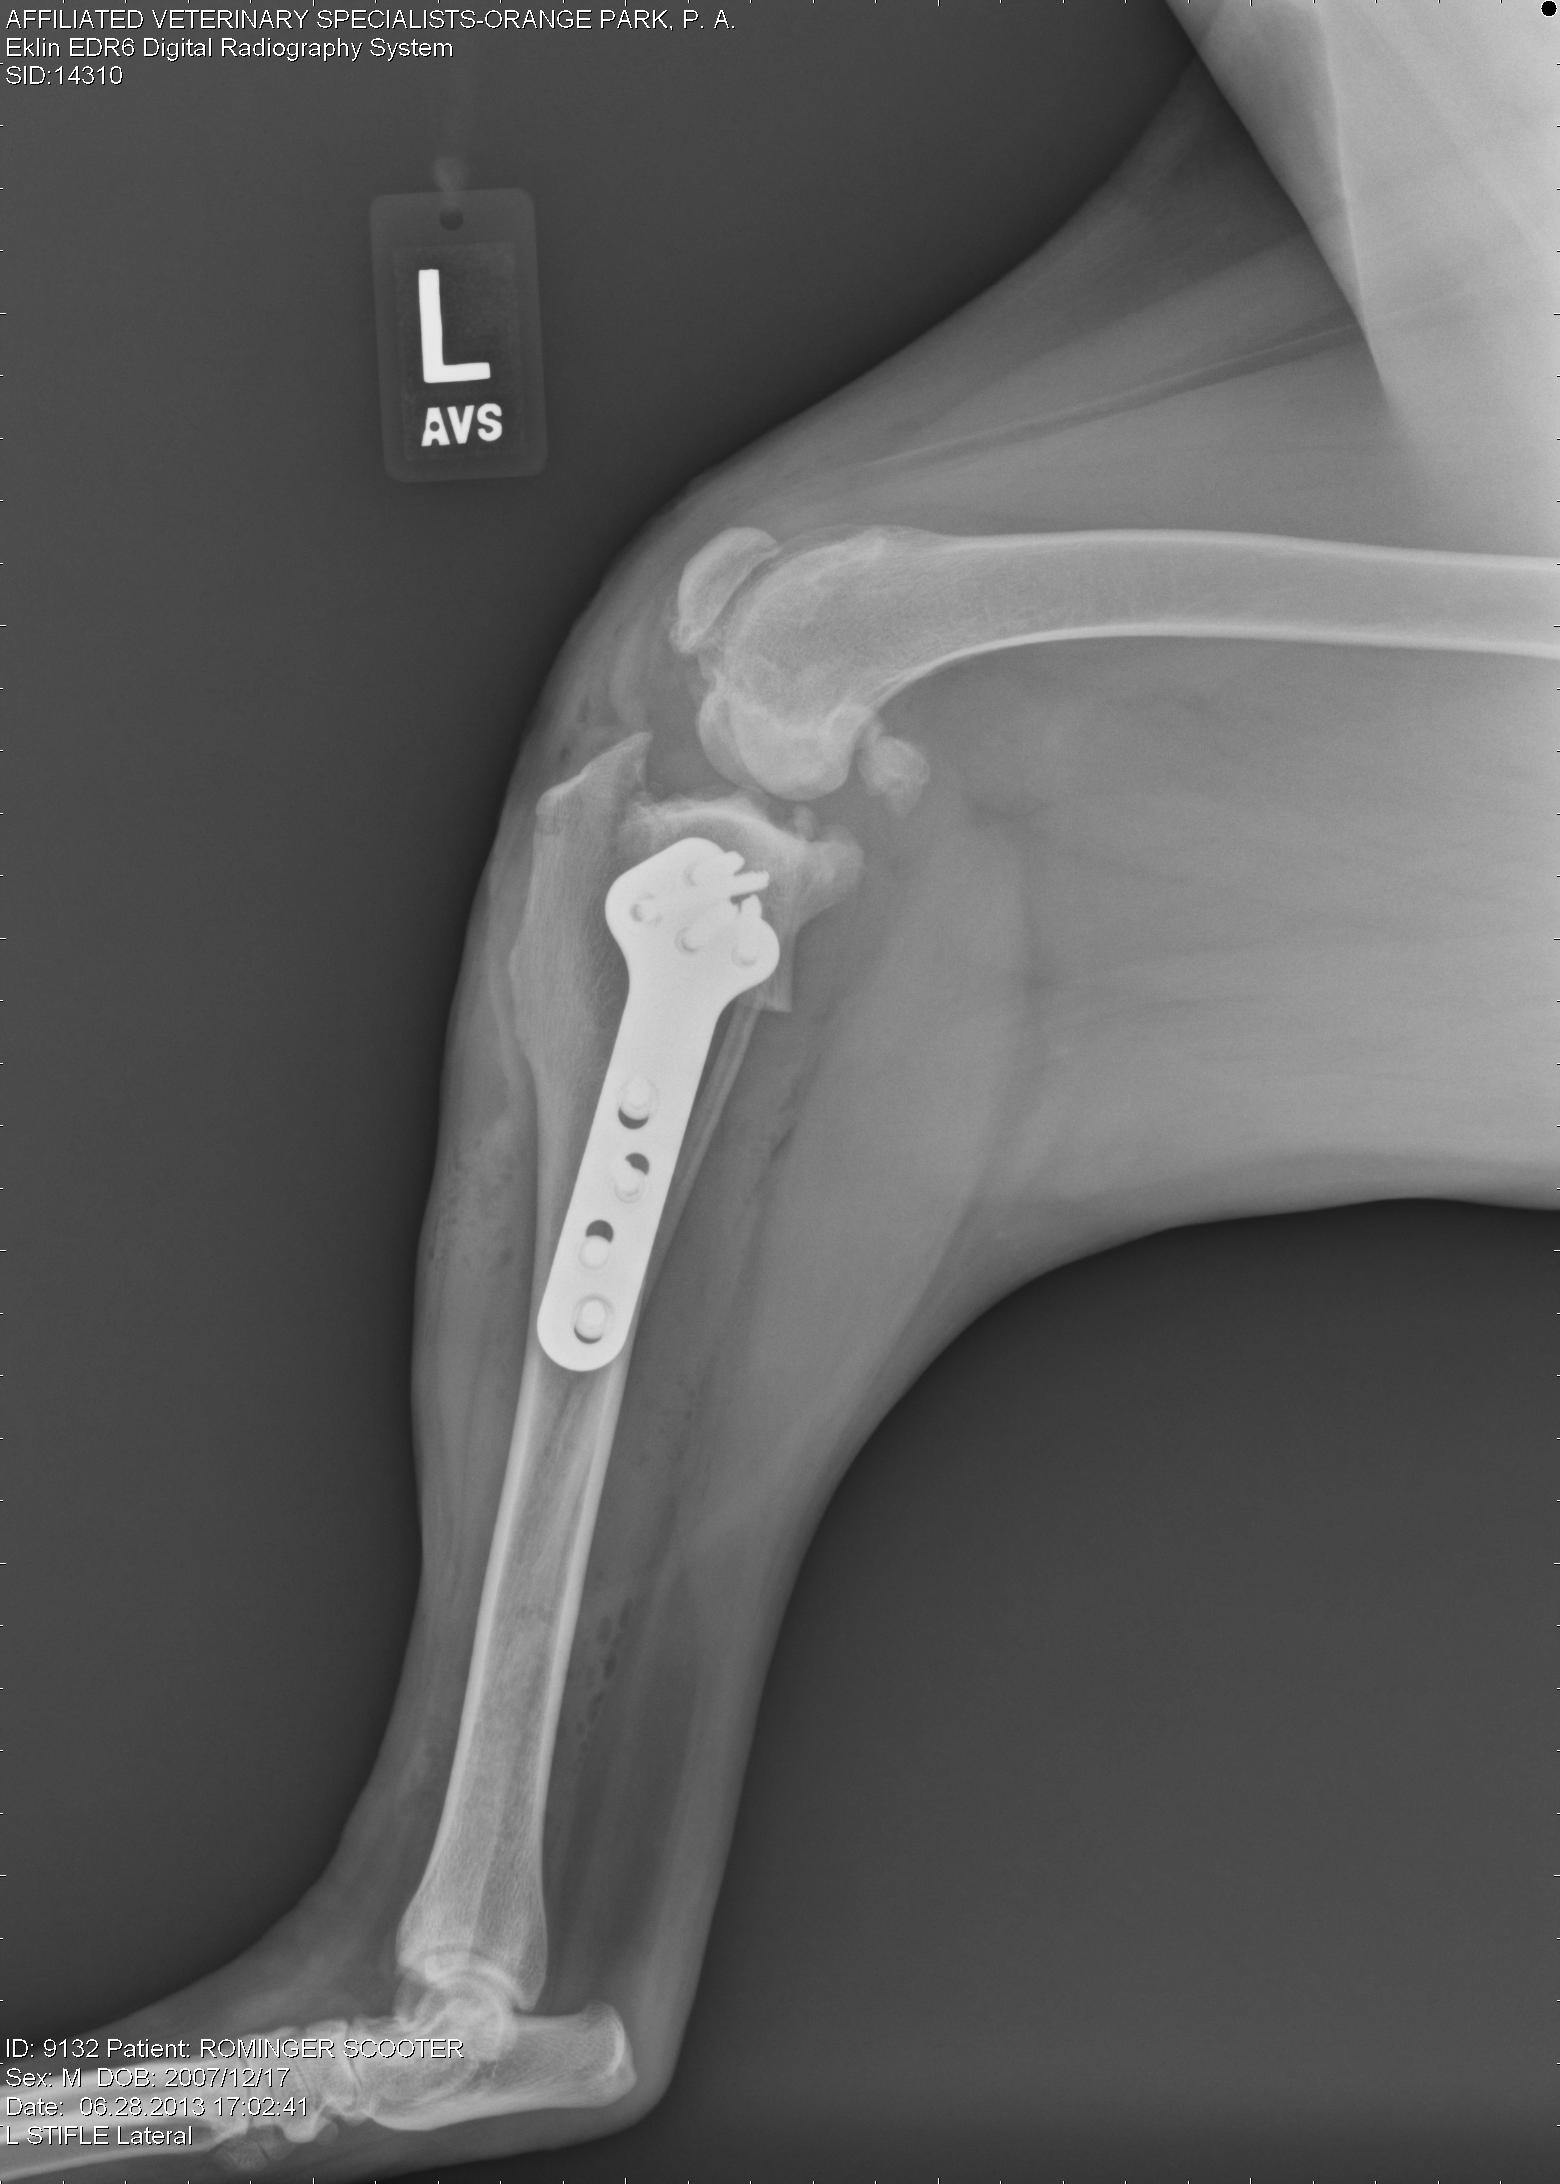

At surgery, bilateral cranial cruciate ligament ruptures were noted, along with bilateral medial meniscal tears. All those findings can be very painful for the patient. Both meniscal tears were debrided (removed) and bilateral tibial plateau leveling osteotomies (TPLOs) were performed. For more detailed information about ways we correct CrCL tears, please view that page on this website.